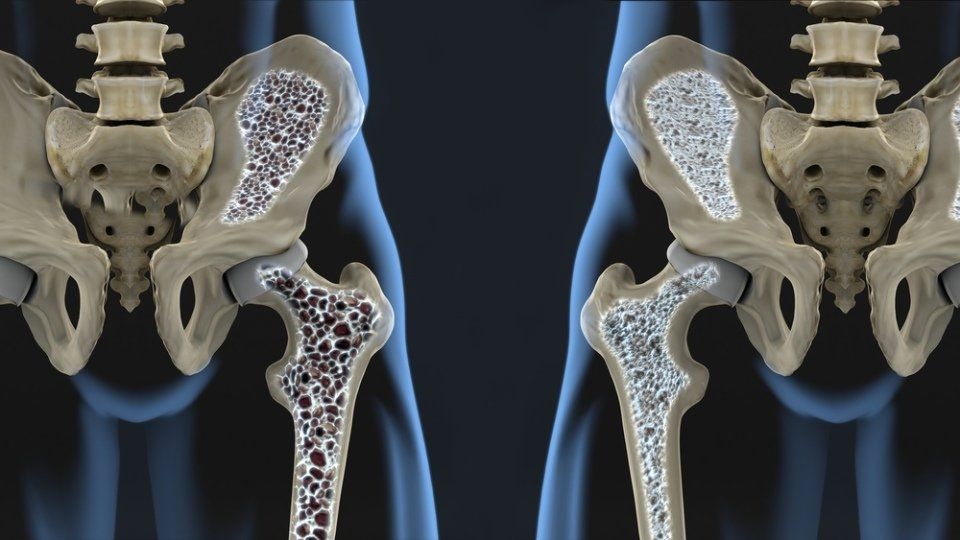

L’osteoporosi è una patologia che colpisce principalmente le donne, manifestandosi soprattutto con l’avanzare dell’età. Consiste in una progressiva riduzione del calcio e della massa ossea, con gravi conseguenze sulla mobilità e un crescente rischio di fratture che riguardano più spesso polso, anca o vertebre.